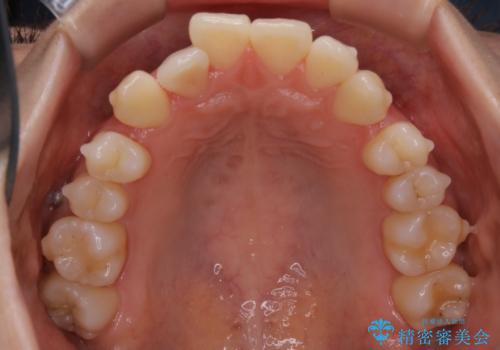

- 前歯のガタつきと噛み合わせの改善を主訴に初診来院され、審査の結果マウスピース装置による非抜歯での矯正を行うこととなりました。

元々の顎骨や口腔・歯槽骨が小さく、どうしても歯が並びきらない状況になっていました。マイクロインプラントという固定源からゴムかけを行うなど、補助装置を活用しながら臼歯部を順番に遠心方向(奥)に移動させていくことで抜歯をしなくても歯が並ぶよう計画を立てました。

歯を並べるスペースを作るために、歯の遠心移動と歯列の拡大、歯自体を少しだけ小さく削る(IPR)という方法を複合的に組み合わせて配列を行いました。遠心移動用のゴムかけにはマイクロインプラントという小さいネジを用いて骨に直接固定源を求めました。